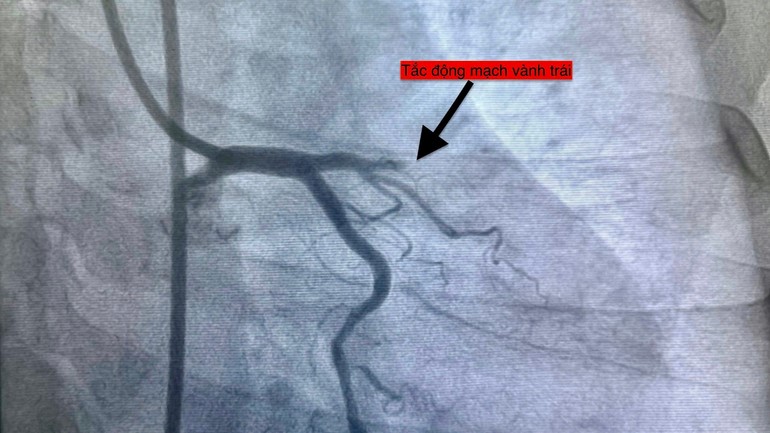

Bốn bệnh nhân với độ tuổi từ 51 đến 78, thuộc nhiều nhóm nguy cơ khác nhau đều nhập viện trong tình trạng cấp cứu và được can thiệp mạch vành kịp thời.

Hình ảnh chụp các ca bệnh nhồi máu cơ tim.